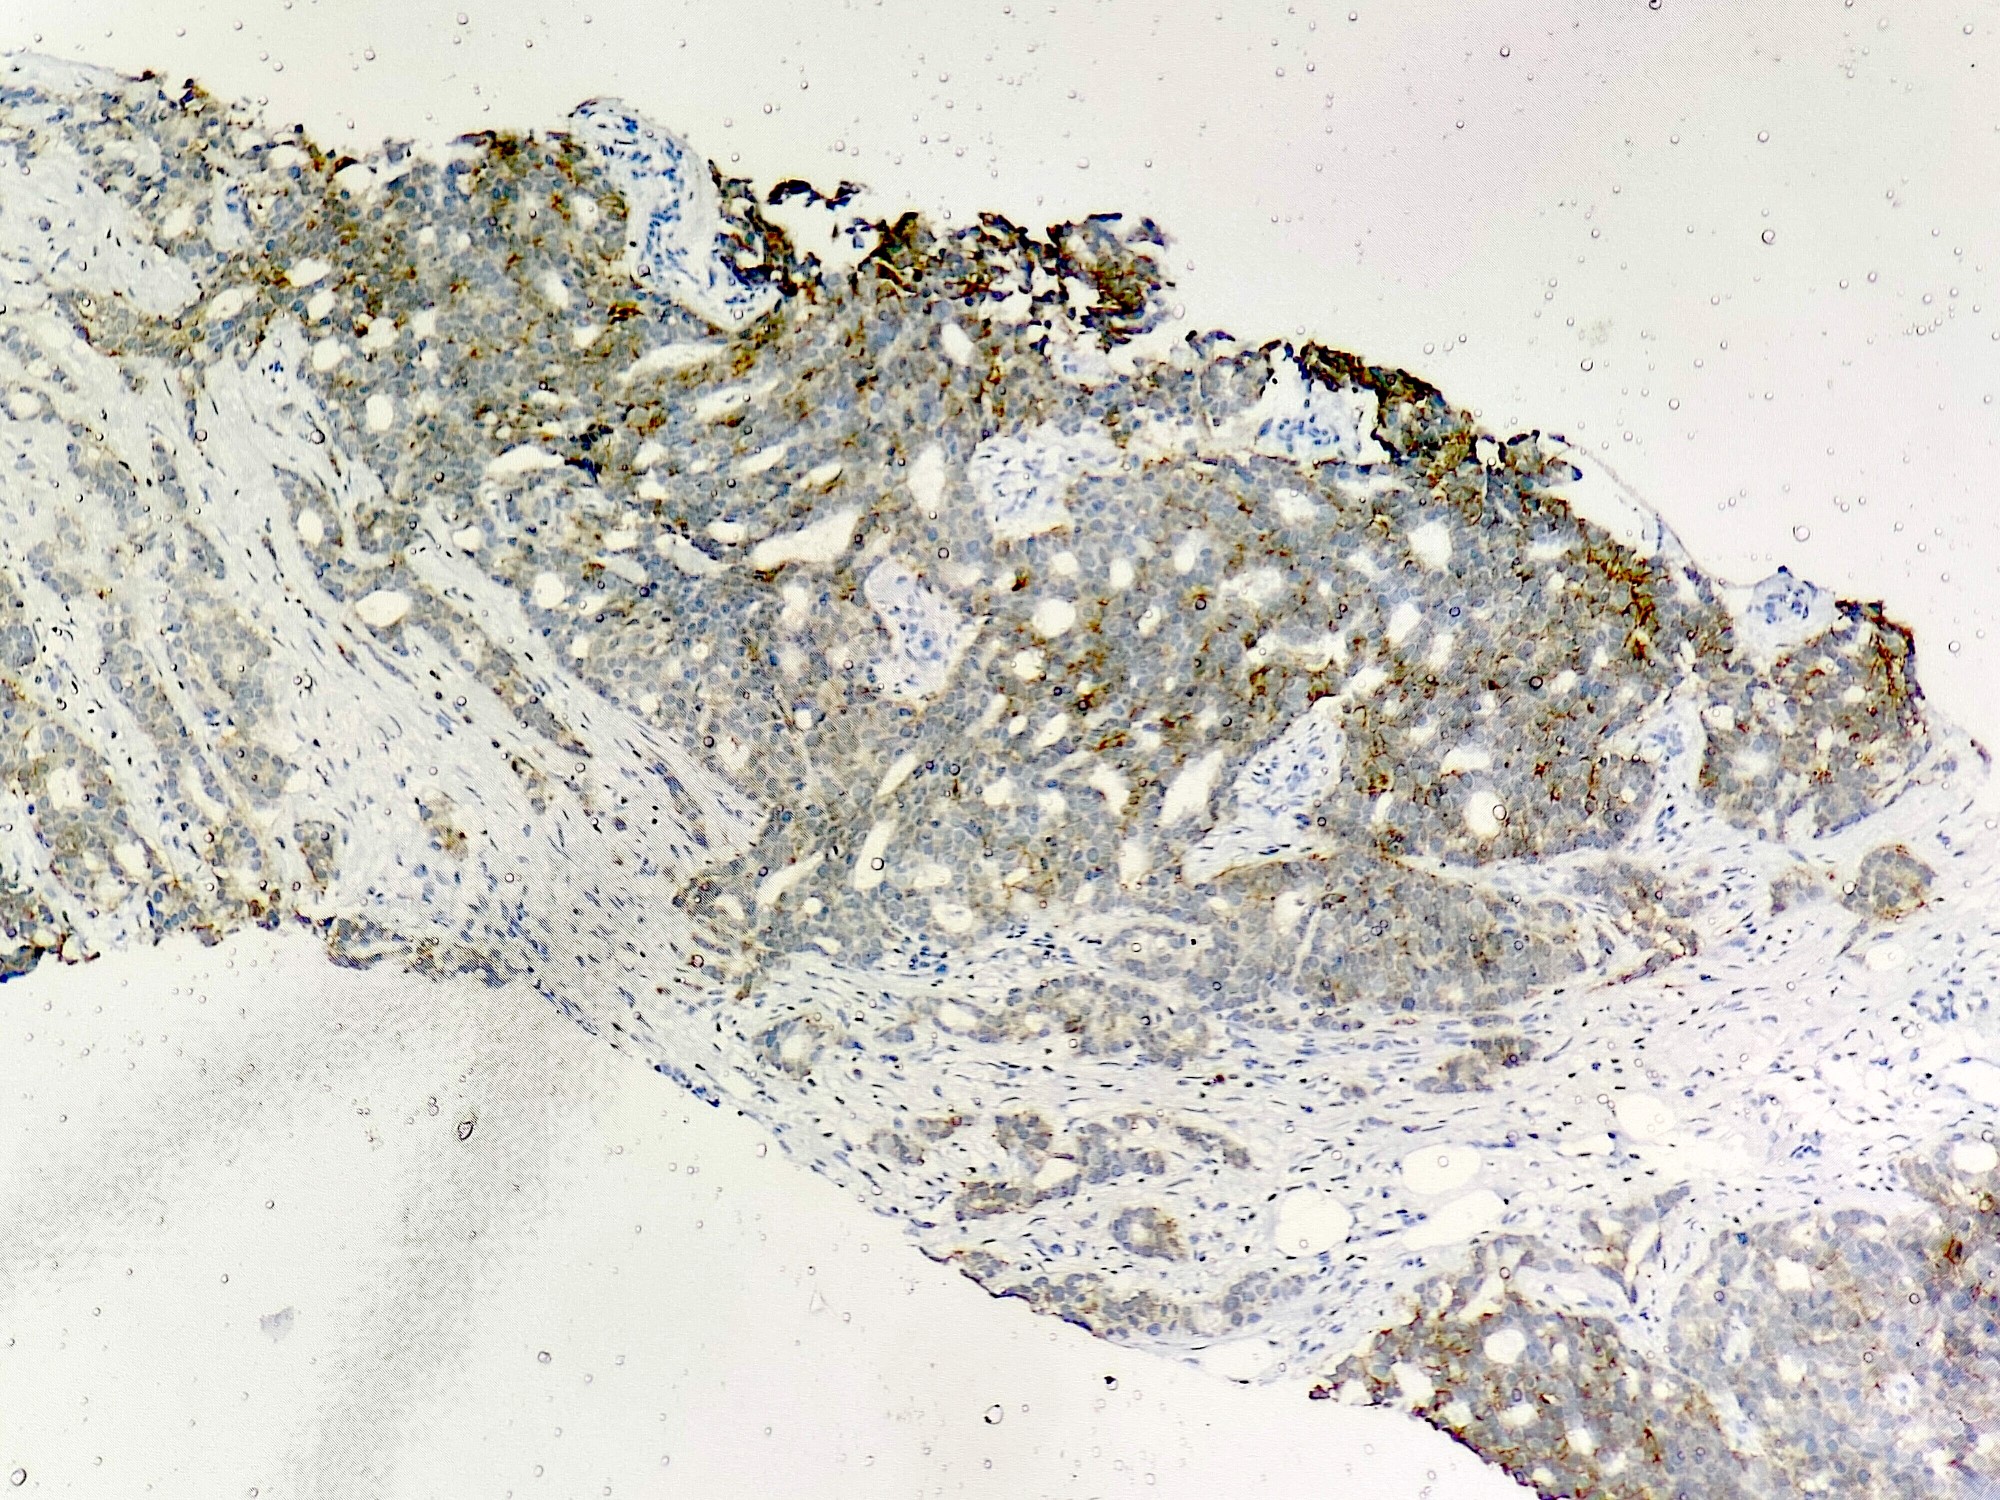

Microscopic (histologic) images

Contributed by Sunitha Shankaralingappa, M.B.B.S, M.D., D.M.

Microscopic (histologic) description

- Irregular cribriform growth pattern > 90% of cells

- Invasive islands or nests of malignant cells with round or angulated contours and well defined cribriform spaces formed by arches of epithelial cells; this gives a sieve-like appearance

- Tumor cells: small, mild / moderate pleomorphism, no nuclear atypia

- No / sparse mitotic activity

- Desmoplastic stroma

- Mucin positive secretion, microcalcifications in lumen

- Myoepithelial cells absent

- Associated with cribriform ductal carcinoma in situ (DCIS)

Negative stains

- HER2

- Myoepithelial markers: distinguish ICC from cribriform DCIS